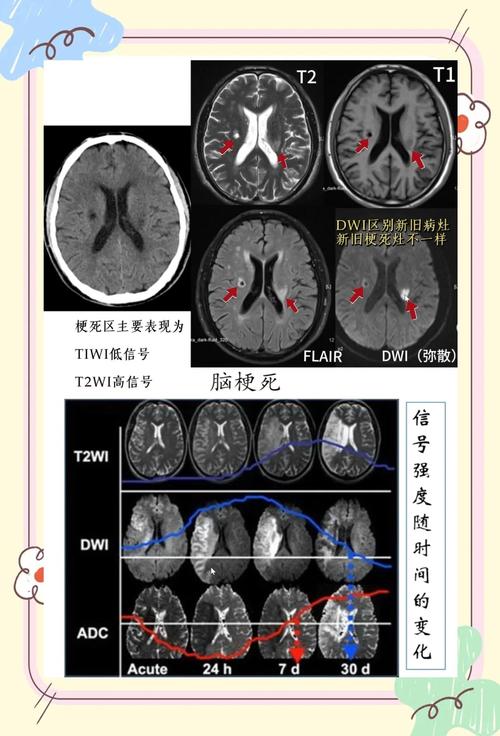

虽然CT快速、便宜、普及,但在诊断脑梗方面,MRI有压倒性优势:

| 特性 | CT (计算机断层扫描) | MRI (磁共振成像) |

|---|---|---|

| 对早期脑梗的敏感性 | 低 (发病6小时内多为阴性) | 极高 (发病30分钟内即可发现) |

| 关键序列 | - | DWI (弥散加权成像),能发现细胞水平的缺血,是诊断早期脑梗的“金标准” |